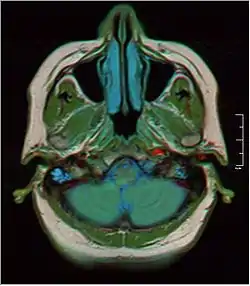

MRI showing fluid in mastoid air cells